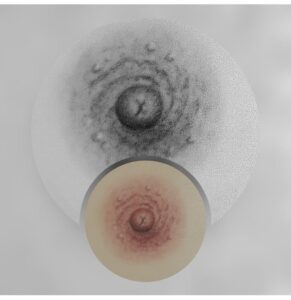

Reconstruction d’aréole mammaire en 3D

La pigmentation réparatrice de l’aréole mammaire permet de recréer visuellement une aréole naturelle après une chirurgie ou dans le cadre d’un parcours de reconstruction. Cette prestation est réalisée avec délicatesse, précision et respect, afin d’obtenir un rendu harmonieux et réaliste.

Tarif avec 1 retouche comprise: 380 € l’une, 600 € les 2